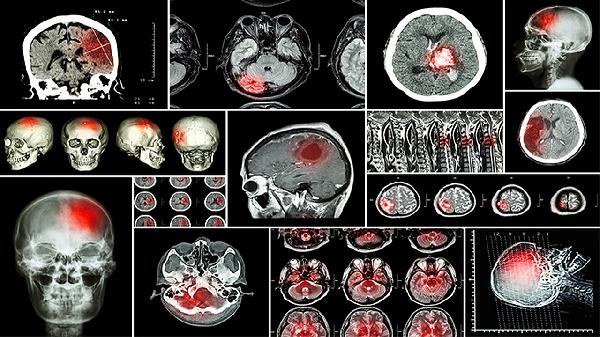

家属需密切监测患者意识状态、瞳孔变化及肢体活动情况。如出现持续头痛加剧、反复呕吐、意识模糊等症状,提示病情可能进展,需立即就医进行CT复查。